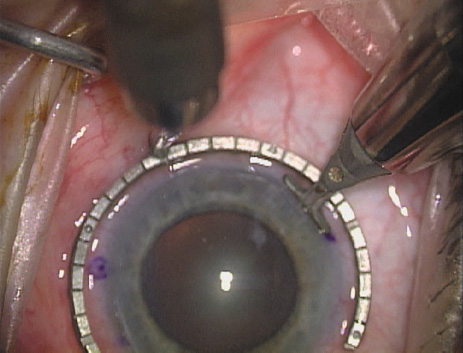

ways. Our preferred method makes use of a modified Fine-Thornton fixation

ring (Nichamin Fixation Ring and Gauge; Mastel Precision, Storz, Rhein

Medical). This instrument serves to fixate and position

the globe in order to optimize incision placement, as well as to delineate

the extent of arc to be incised. One visually extrapolates from

the limbus to marks on the surface of the ring. Each incremental mark

is 10 degrees apart, and bold hash marks (180 degrees) opposite

to each other serve to align and center the incision over the steep

meridian. This approach obviates the need to ink and physically mark

the cornea. If one desires, particularly when first gaining experience

with LRIs, a two-cut RK marker may be used to place ink marks upon the

cornea to show the exact extent of arc that is to be incised, in conjunction

with the fixation ring/gauge (Fig. 4). Alternatively, various press-on markers are available, such as

markers, rings, and blades for performing LRIs.  Fig. 4. The Nichamin Fixation Ring and Gauge serves to both fixate the globe and

delineate the extent of arc to be incised; a two-cut radial marker may

be used to mark the extent of arc to be incised, and the Mastel Nichamin

Force AK Diamond Blade with preset depth of 600 microns. Fig. 4. The Nichamin Fixation Ring and Gauge serves to both fixate the globe and

delineate the extent of arc to be incised; a two-cut radial marker may

be used to mark the extent of arc to be incised, and the Mastel Nichamin

Force AK Diamond Blade with preset depth of 600 microns.